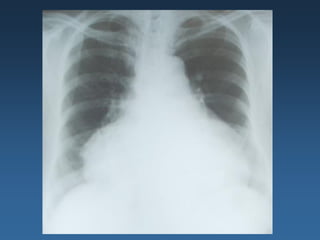

Radiografia Tórax: Aumento de área cardíaca, padrão de inversão

de trama vascular, discreto derrame pleural a direita.

EXAMES – RADIOGRAFIA DE TÓRAX

INDICE CARDIOTORÁCICO

Linhas de Kerley: são finas

opacidades lineares

pulmonares causadas por

fluido ou infiltração do

interstício pulmonar.

Aumento da área cardíaca

Pulmões

Redistribuição do desenho vascular

Borramento hilar

infiltrado intersticial

Linhas B de Kerley

Edema alveolar

Derrame pleural